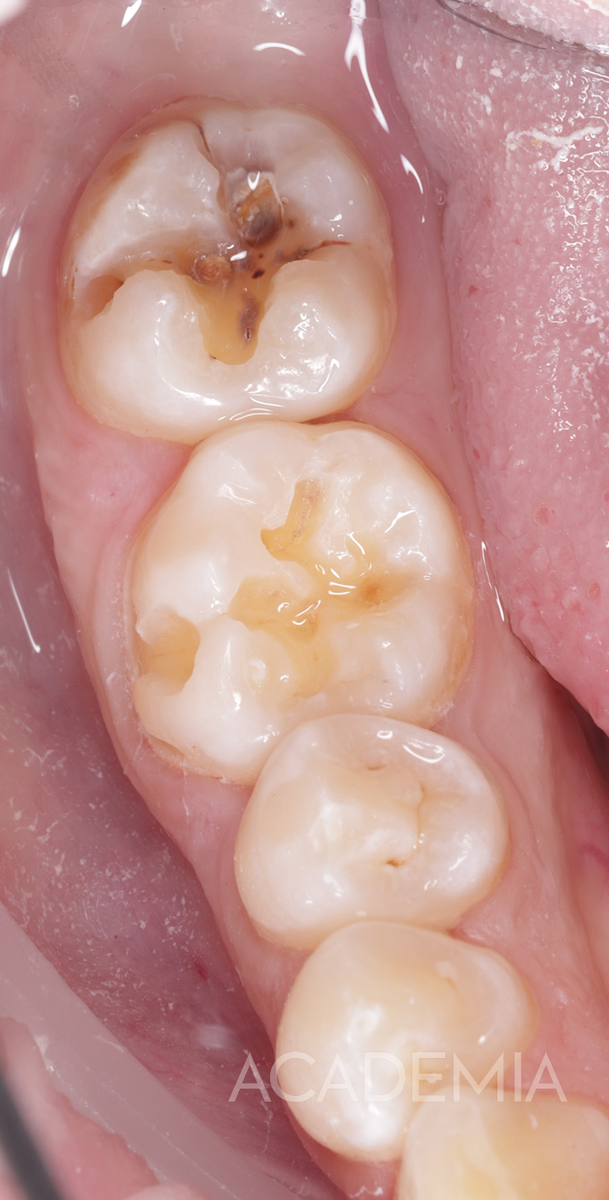

Как распознать глубокий кариес

Вот основные признаки, на которые стоит обратить внимание:

• ощутимая полость в зубе (часто темного цвета),

Как проходит лечение глубокого кариеса

Лечение глубокого кариеса зубов требует максимальной аккуратности.

Задача врача — удалить все ткани, пораженные кариесом, и при этом не вскрыть пульповую камеру, в которой находится нерв.

Использование микроскопа или бинокулярной оптики в этой процедуре является большим плюсом, так как доктор гораздо эффективнее контролирует процесс. При увеличении врач видит всё в разы лучше, минимизируя риск повреждения пульпы и снижая вероятность осложнений.